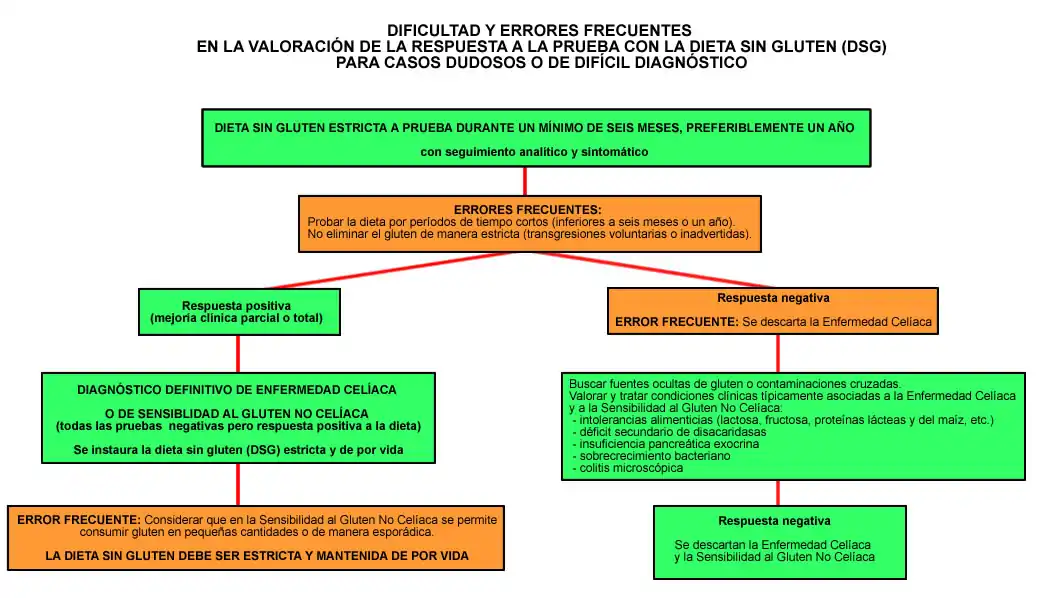

d) Hacer un tratamiento de prueba con dieta sin gluten (DSG) durante 6 meses mínimo, preferiblemente un año, observando la respuesta clínica, así como los cambios analíticos y serológicos (la más aconsejable).

En casos dudosos, está plenamente justificado el instaurar una dieta sin gluten estricta durante un plazo mínimo de seis meses, realizando seguimiento clínico y analítico adecuados, para analizar la respuesta (“diagnóstico ex-iuvantibus”).[45]

El diagnóstico de enfermedad celíaca se confirma cuando existe una respuesta positiva a la DSG, que se calcula en un plazo medio de 6 meses.[27]

Cuando no se produce la mejoría esperada con la dieta sin gluten o esta se demora, hay que valorar muy cuidadosamente la presencia de otras intolerancias alimenticias asociadas (lactosa, fructosa, etc.) porque con la simple toma de leche sin lactosa puede mejorarse o la restricción de algún tipo de fruta. Otras causas de no mejoría son la presencia del llamado “gluten oculto” en algunos productos no bien etiquetados, así como las “contaminaciones cruzadas” comiendo en la mesa con otras personas que toman pan de trigo y desmigan con frecuencia de forma inadvertida, alimentos contaminados con migas o restos de harina durante su preparación o manipulación, etc.[163]

En dichos casos, se debería proponer la realización de una dieta sin gluten (DSG) de prueba durante un mínimo de 6 meses, preferiblemente un año, con controles clínicos y analíticos antes y después de la retirada del gluten.[27][45] Se aconseja probar la DSG durante unos 6 meses como mínimo, preferiblemente un año, ya que con menos tiempo los cambios no se producen de forma significativa, sobre todo en pacientes que llevan padecimientos clínicos prolongados.

La DSG debe ser estricta, eliminando de la alimentación todos los productos que contengan o se cocinen con harina de trigo, centeno, cebada y avena (dieta TACC), que son los cuatro cereales con gluten, y sustituyéndolos por harina de maíz y arroz sin trazas de gluten, evitando contaminaciones inadvertidas y todo tipo de transgresiones dietéticas.

Con dicha dieta de prueba, en la mayoría de los casos, se produce una mejoría clínica significativa, con desaparición prácticamente total de la mayoría de las molestias, que se confirma además con una mejoría o normalización de la mayor parte de las alteraciones analíticas, previamente existentes.

Gracias a la realización de esta DSG, se confirmará el diagnóstico de enfermedad celíaca en la mayor parte de los casos previamente etiquetados como dudosos.

Consideraciones importantes sobre la prueba con la dieta sin gluten

En caso de no mejoría, antes de abandonar la prueba con la dieta sin gluten, hay que hacer una valoración muy cuidadosa tanto clínica como analítica, para tratar de evitar posibles errores de interpretación. Ver sección Mala respuesta a la dieta y persistencia de síntomas.

En la valoración de la respuesta a la prueba con la dieta sin gluten

Cuando se utiliza la prueba con la dieta sin gluten (DSG) como método diagnóstico de los casos dudosos y no se produce ninguna mejoría, antes de abandonarla hay que hacer una valoración muy cuidadosa tanto clínica como analítica, para tratar de evitar posibles errores de interpretación.